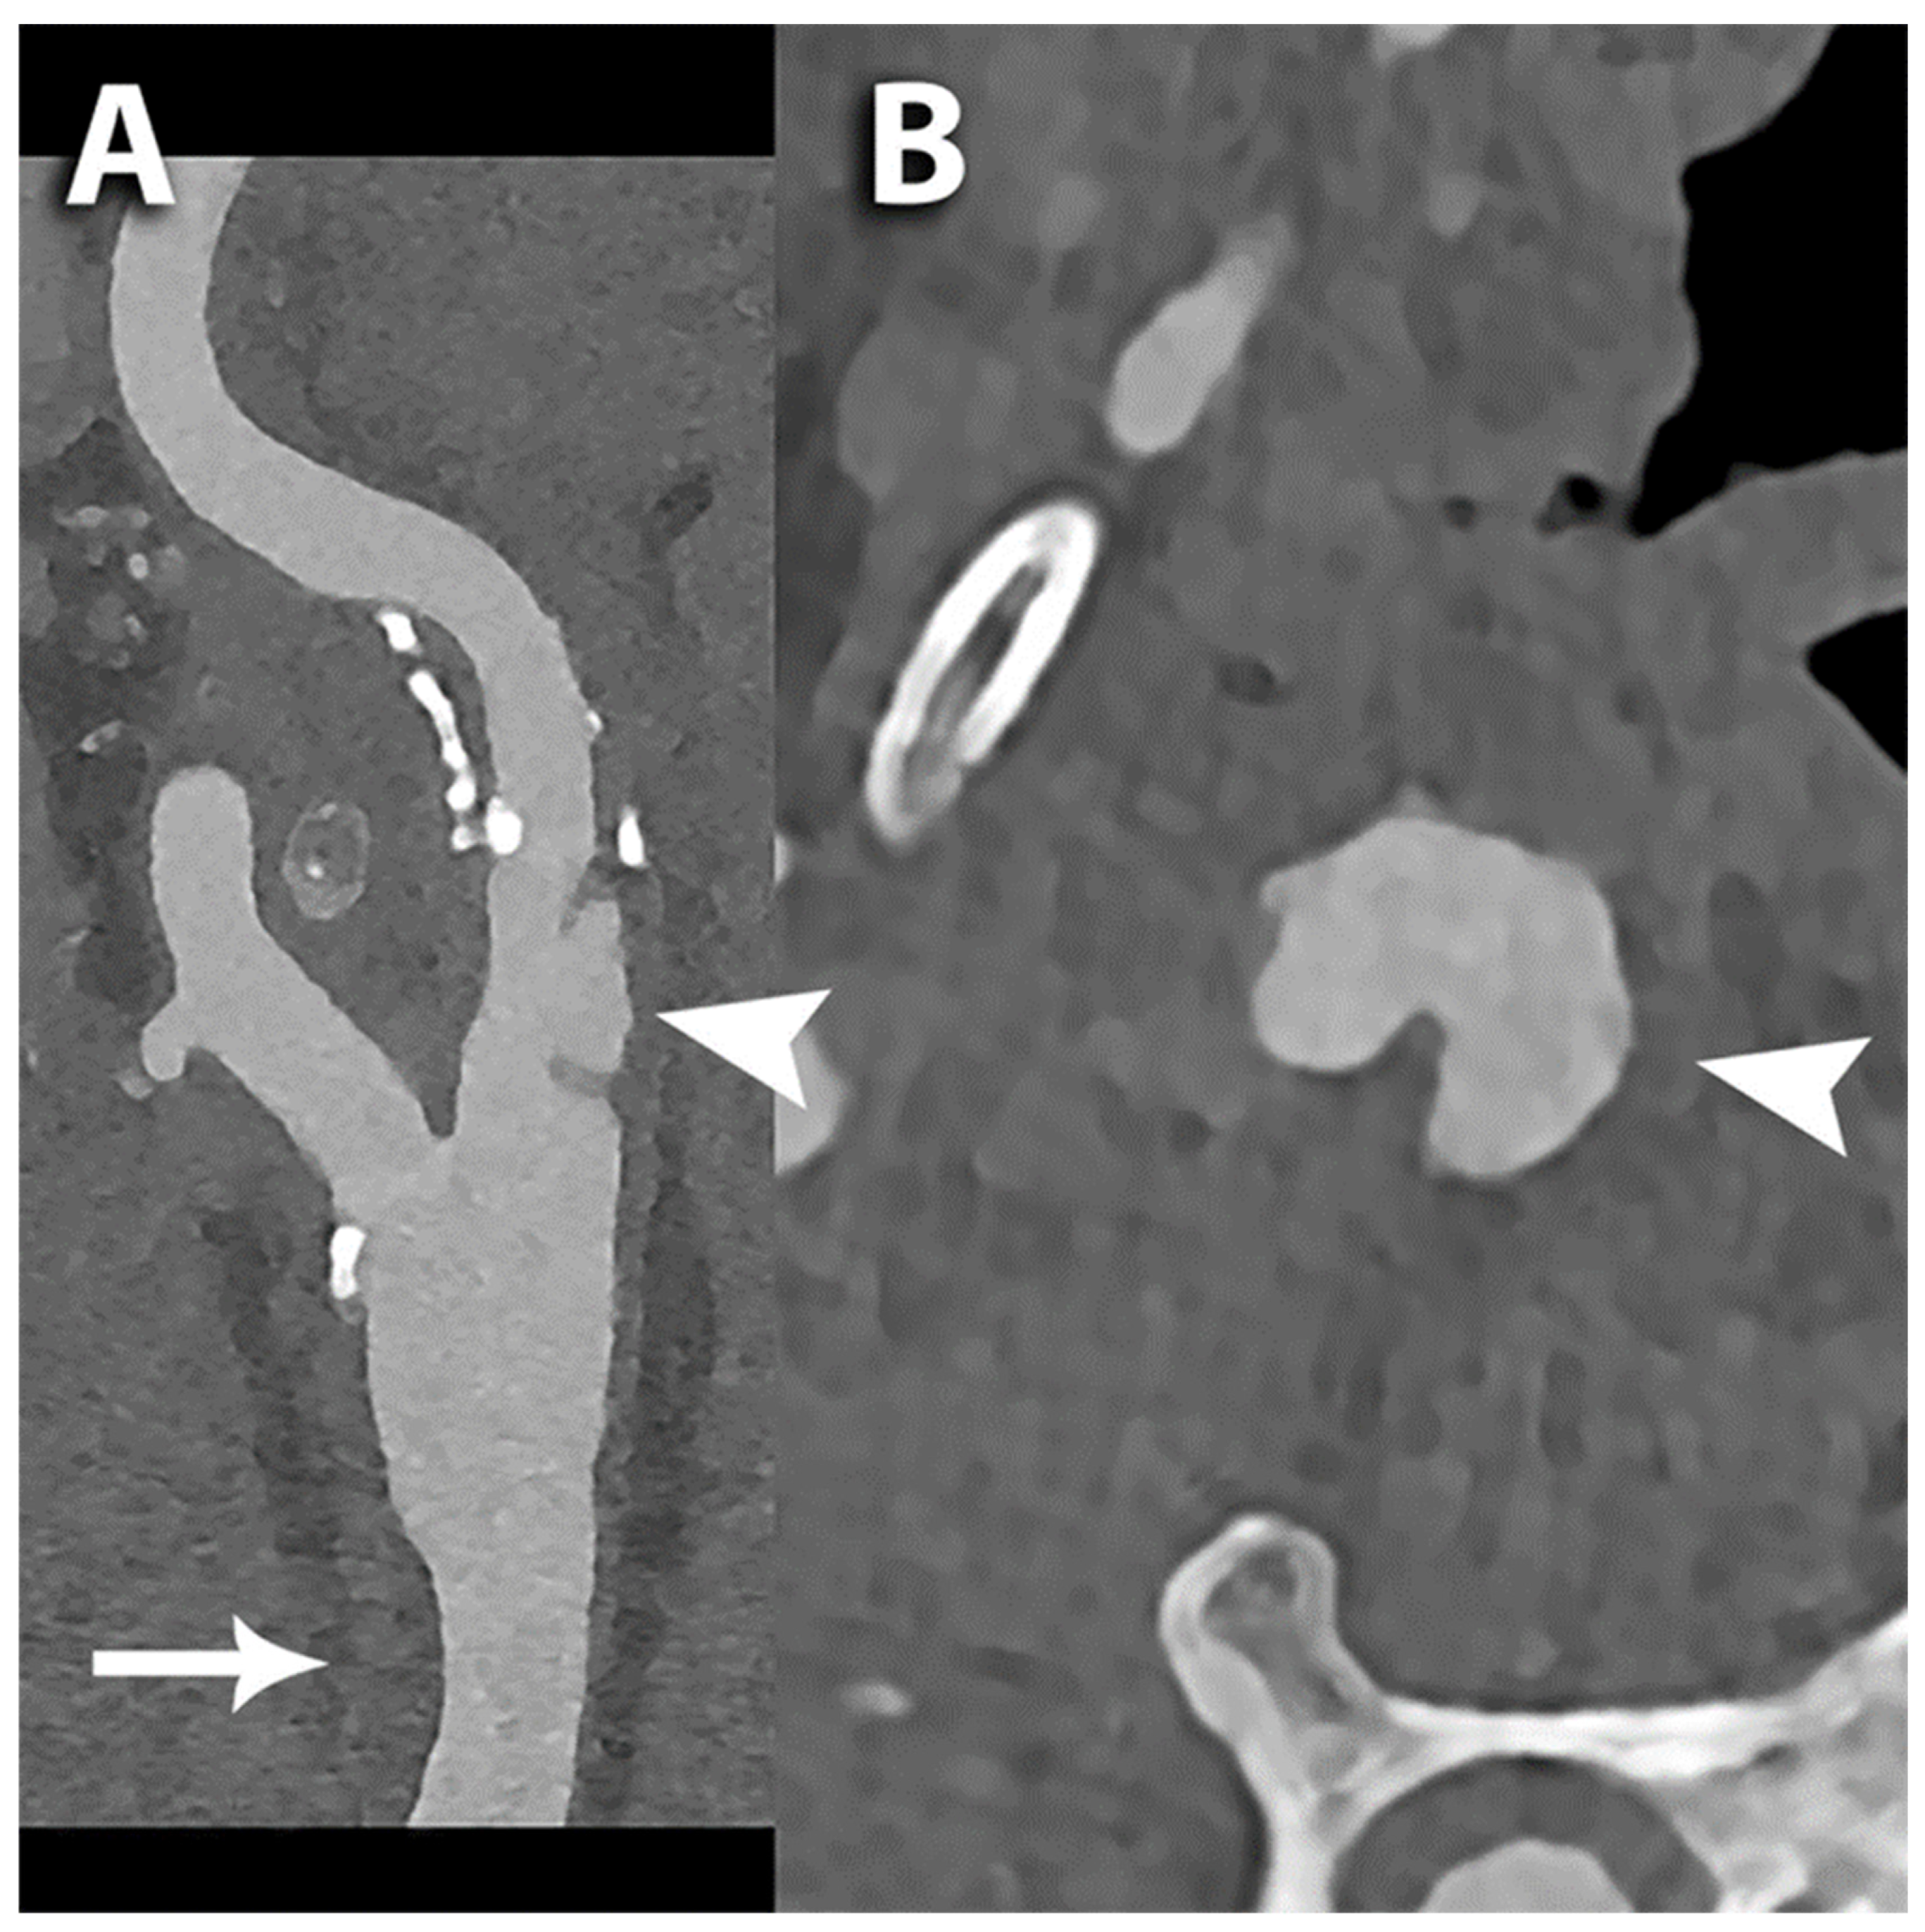

- Keser, Z.; Diehn, F.E.; Lanzino, G. Photon-Counting Detector CT Angiography in Cervical Artery Dissection. Stroke 2024, 55, e48–e49. [Google Scholar] [CrossRef] [PubMed]